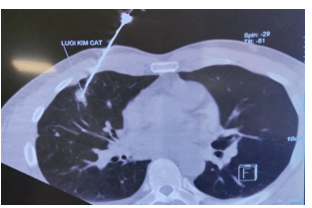

Hình 2: Hình ảnh chọc sinh thiết tổn thương vùng phổi phải dưới hướng dẫn chụp cắt lớp vi tính lồng ngực

Bệnh nhân đươc sinh thiết u làm giải phẫu bệnh có kết quả: Ung thư biểu mô tuyến, được làm các đột biến Gen có kết quả: ALK (+), EGFR (-), PD -L1 <1%